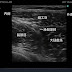

腕神経叢ブロックの鎖骨上アプローチでのプローブの位置から、走査面を前下方にしゃくりあげるようにすると、鎖骨上窩で鎖骨下静脈を描出できる。この鎖骨下静脈をさらに内側に追っていくと、鎖骨下静脈が無名静脈に合流する部分が描出される。この部位で、無名静脈穿刺をしてもよい。

| 鎖骨上窩から鎖骨下静脈を描出。 画面の右が外側、左が内側 |